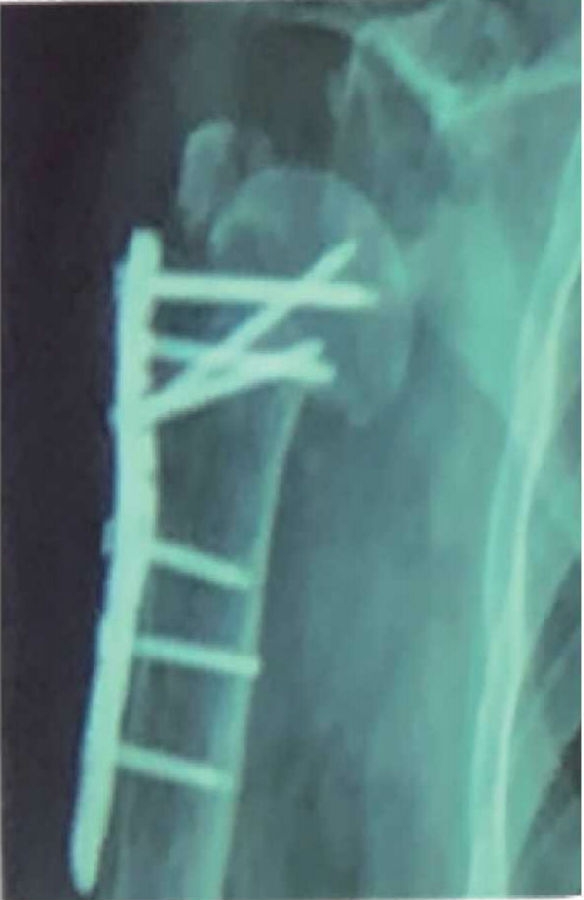

肱骨近端骨折内固定术后整体并发症发生率为30%。其中,常见的并发症主要有螺钉切出/穿透关节面、肱骨头内翻畸形、肱骨头缺血坏死、髓内钉移位、骨折不愈合、内固定断裂等(图1~3)。

图1 骨近端骨折术后不愈合、肱骨头内翻